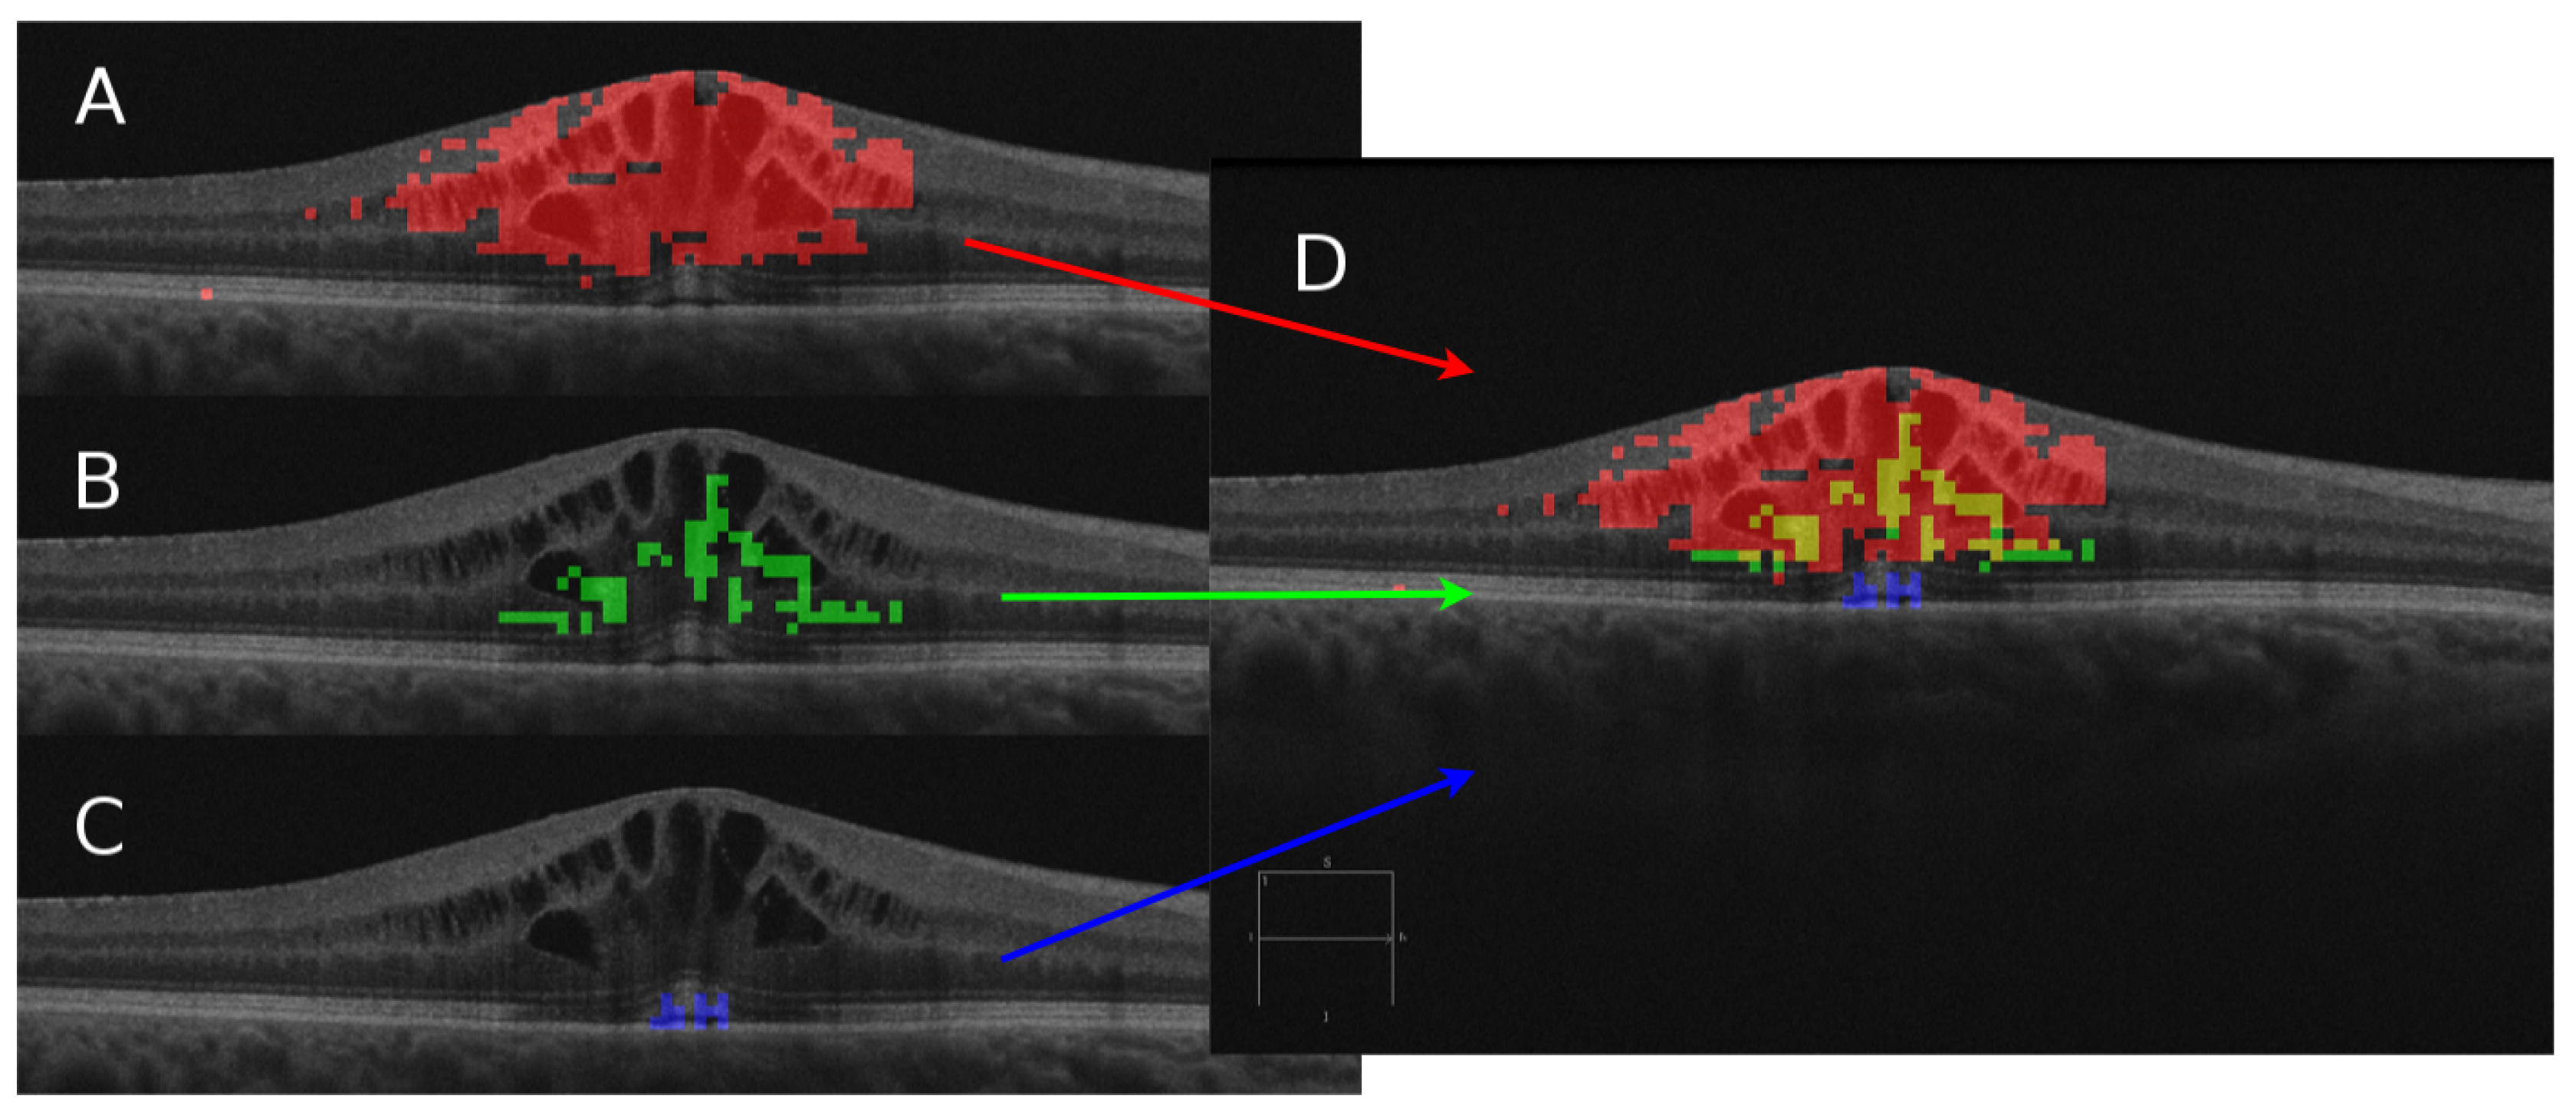

Automatic Tool for the Detection, Characterization and Intuitive Visualization of Macular Edema Regions in OCT Images †